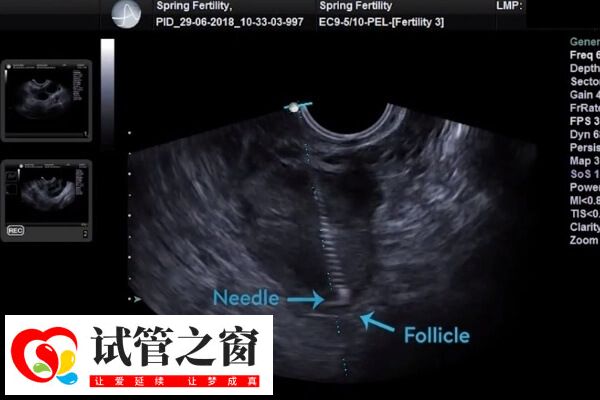

对于腹水较多且症状明显的患者,可在医生指导下进行穿刺引流,以快速排除腹水。在严重情况下,可能需要手术干预,如卵巢囊肿抽吸等。